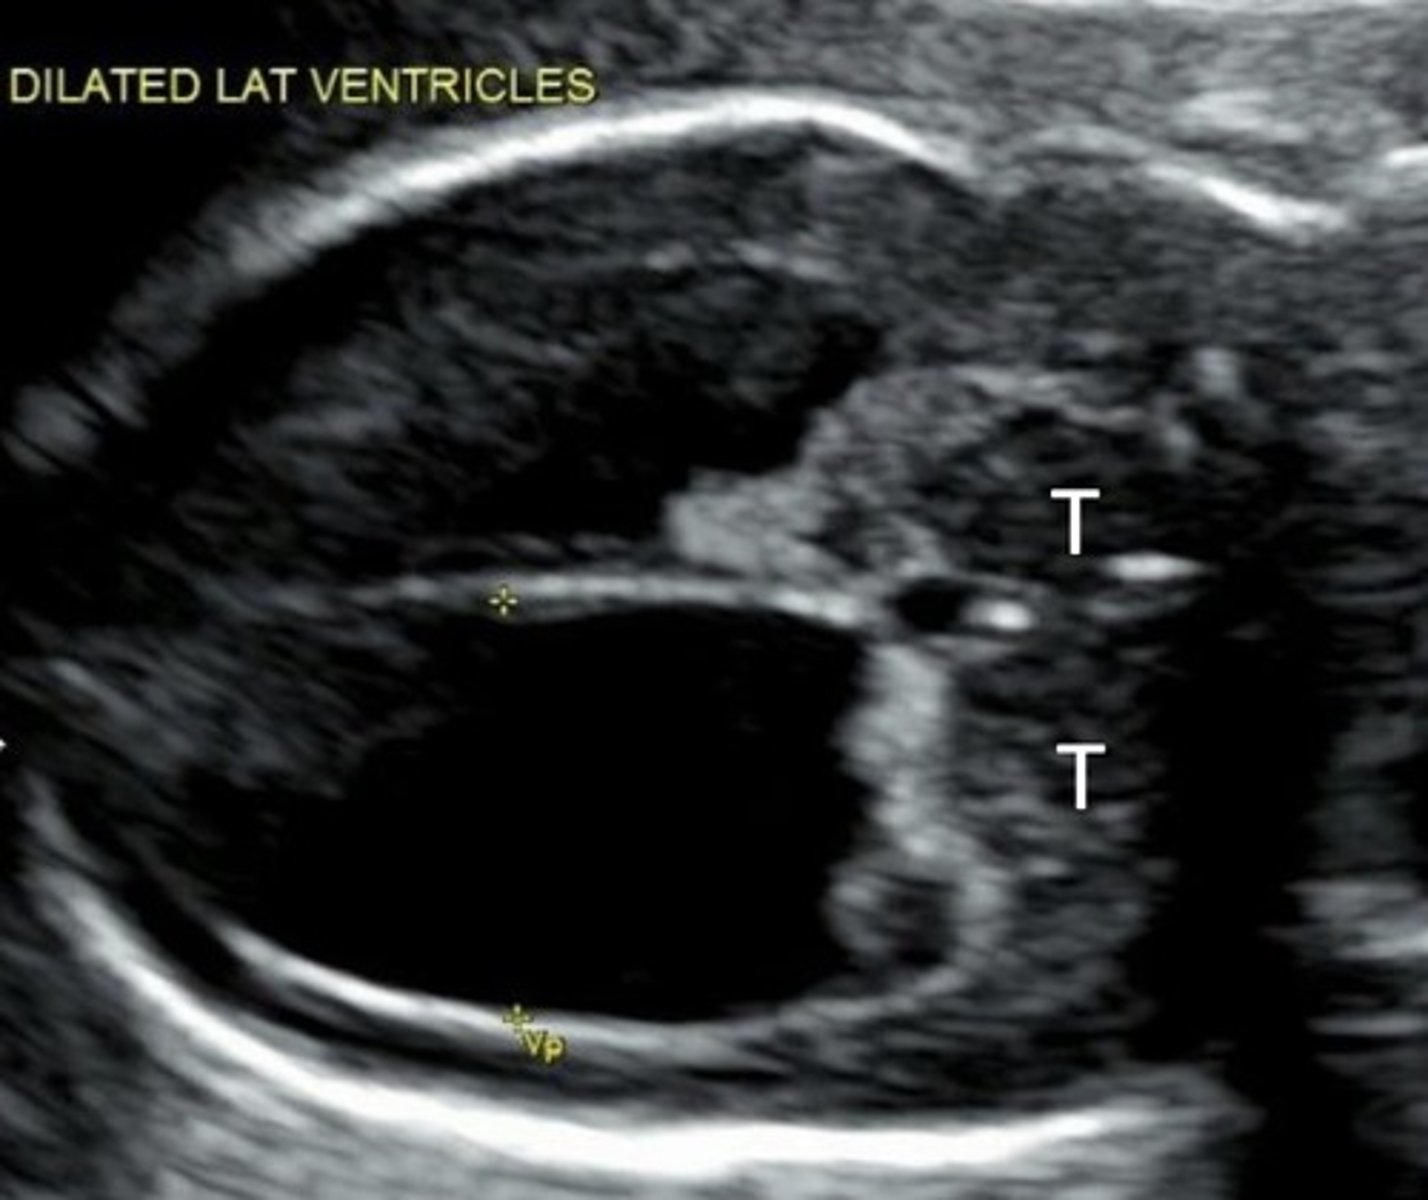

Hydrocephalus

Dilated ventricles

Dangling choroid plexus

Enlarged head